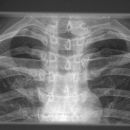

Clavicula

Panoramaaufnahme

Technik

• FDA: 1,15 m

• Ausgangsformat: 24/30 2x

• mit Raster

• Gewichte jeweils ~ 5kg

Lagerung

Mit dem Rücken am Stativ

Arme hängen nach unten und werden, je nach Anforderung, mit Gewichten belastet

Der Patient darf die Gewichte nicht aktiv halten, sondern sie werden durch Manschetten am Handgelenk befestigt

Es dürfen die Schulter nicht gehoben werden

Schultern immer hängen lassen

Zentralstrahl

Senkrecht auf Jugulum bei Gesamtaufnahme

oder auf eine Seite zentrieren und das für die andere Seite ebenfalls

Bemerkung

Bei einseitiger Belichtung müssen insgesamt zwei Aufnahme unter ständiger Belastung erfolgen.

Qualitätskriterien

Überlagerungsfreie und (besonders bei Fragestellung Verletzung) in der Projektion gut seitenvergleichbare Abbildung der Acromioclaviculargelenke.